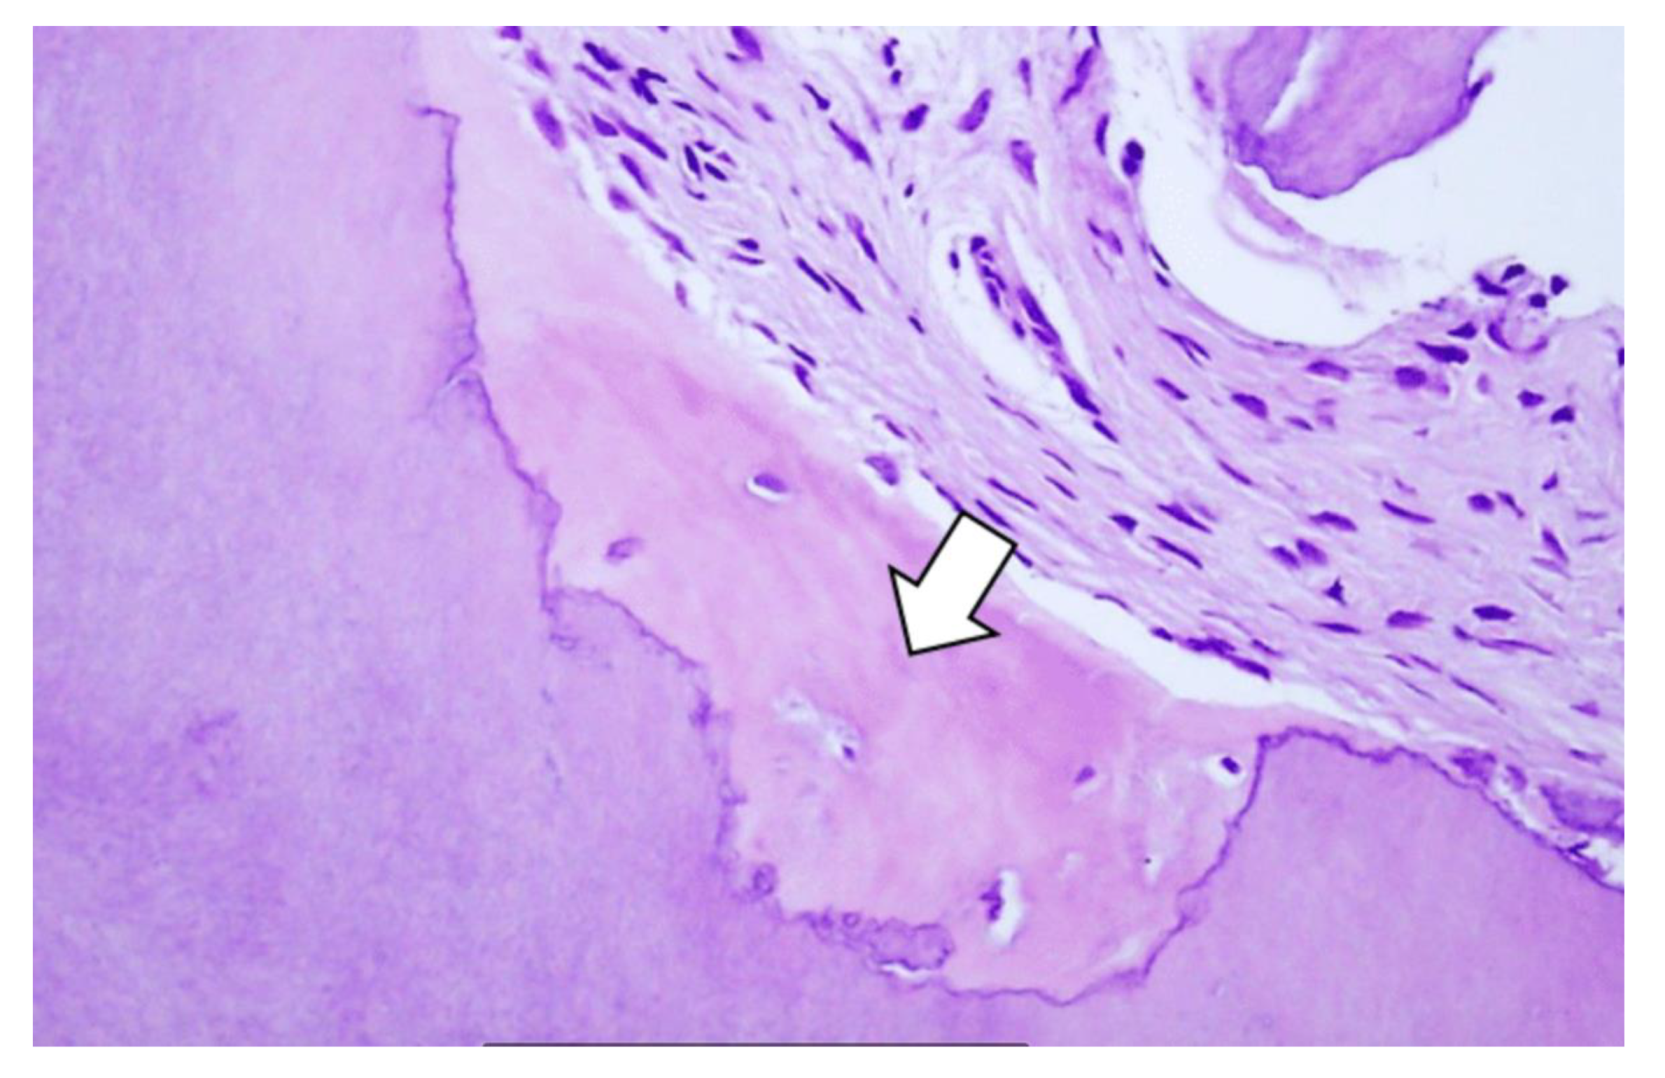

2.5. Histologic Examination